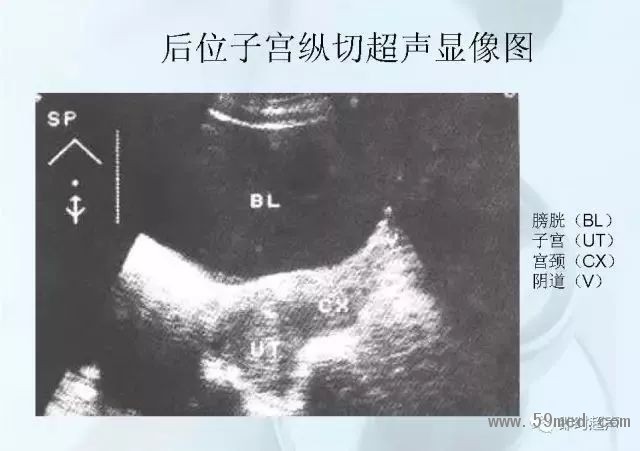

新聞中心 收藏!正常B超解剖圖譜,超實用!

![]() ![]() ![]() ![]() ![]() ![]() ![]() ![]() ![]() ![]() ![]() ![]() ![]() ![]() ![]() ![]() ![]() ![]() ![]() ![]() ![]() ![]() ![]() ![]() ![]() ![]() ![]() ![]() ![]() ![]() ![]() ![]() ![]() ![]() ![]() ![]() ![]() 【注:本文來源于即時超聲,版權(quán)歸原作者所有,如有侵權(quán) 請聯(lián)系 速刪】 =========================== 【閱精彩*悅分享】隨手點擊轉(zhuǎn)至朋友圈,與大家一起分享精彩資訊!當(dāng)然您也可以通過以下方式找到我,與您共同分享藍(lán)韻影像超聲的更多精彩!微信號:landultrasound 電話:+86-0755-66869896 24小時客服熱線:400-888-6452